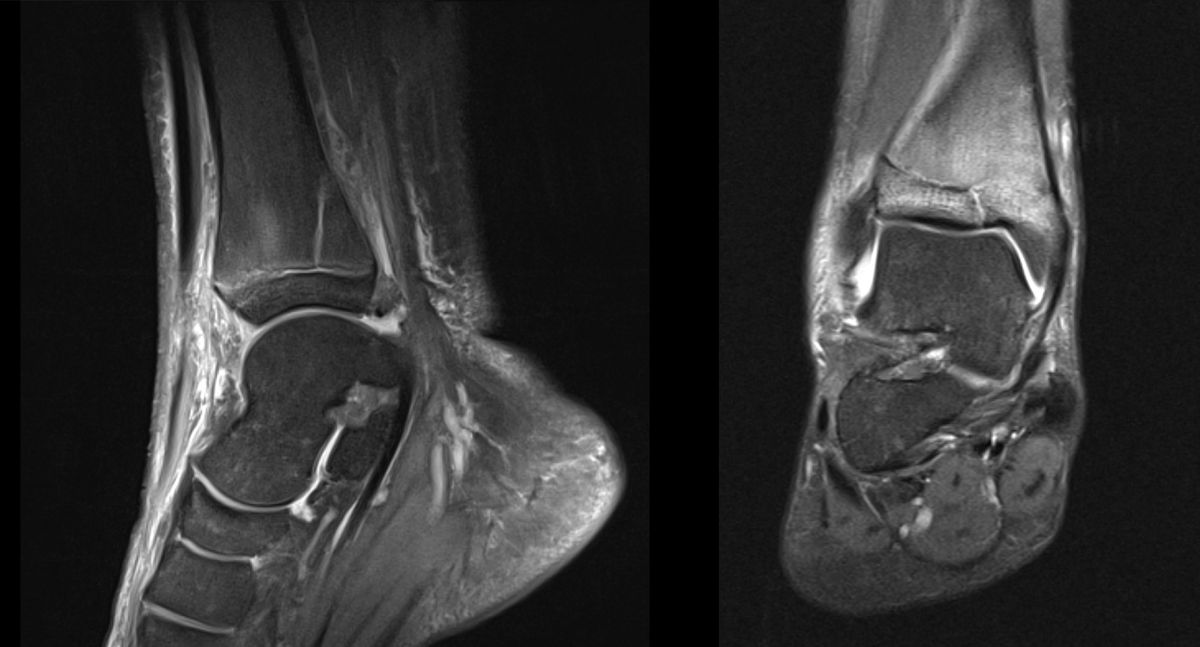

MRT

Die Kernspintomographie hat ihre Stärke in der Darstellung von Weichteilverletzungen. Insbesondere Verletzungen der Wachstumsfuge, des Periosts und der Bänder lassen sich gut visualisieren. Nachteilig ist die Untersuchungsdauer von 20-30 Minuten. Bleibt das Kind während dieser Zeit nicht ruhig liegen, kommt es zu Bewegungsartefakten, welche die Beurteilbarkeit der Bilder beeinträchtigen.

Osteochondrale Verletzungen können infolge eines Distorsionstraumas beobachtet werden (Taluskantenfraktur), teilweise lässt sich auch kein Trauma eruieren. Der es sich bei osteochondralen Verletzungen um keine Arthrose handelt, ist gerade bei Schmerzfreiheit ein defensives Vorgehen angezeigt. Bei offenen Wachstumsfugen kann eine osteochondrale Verletzung unter konservativer Therapie ausheilen.

Eine retrograde Anbohrung ist indiziert, wenn sich im MRT Verlauf eine zunehmende Sklerosierung im Randbereich der Läsion zeigt bei intakter Knorpeloberfläche.

Instabile Knorpelareale werden arthroskopisch entfernt in Verbindung mit einer Mikrofrakturierung der subchondralen Knochenlamelle.